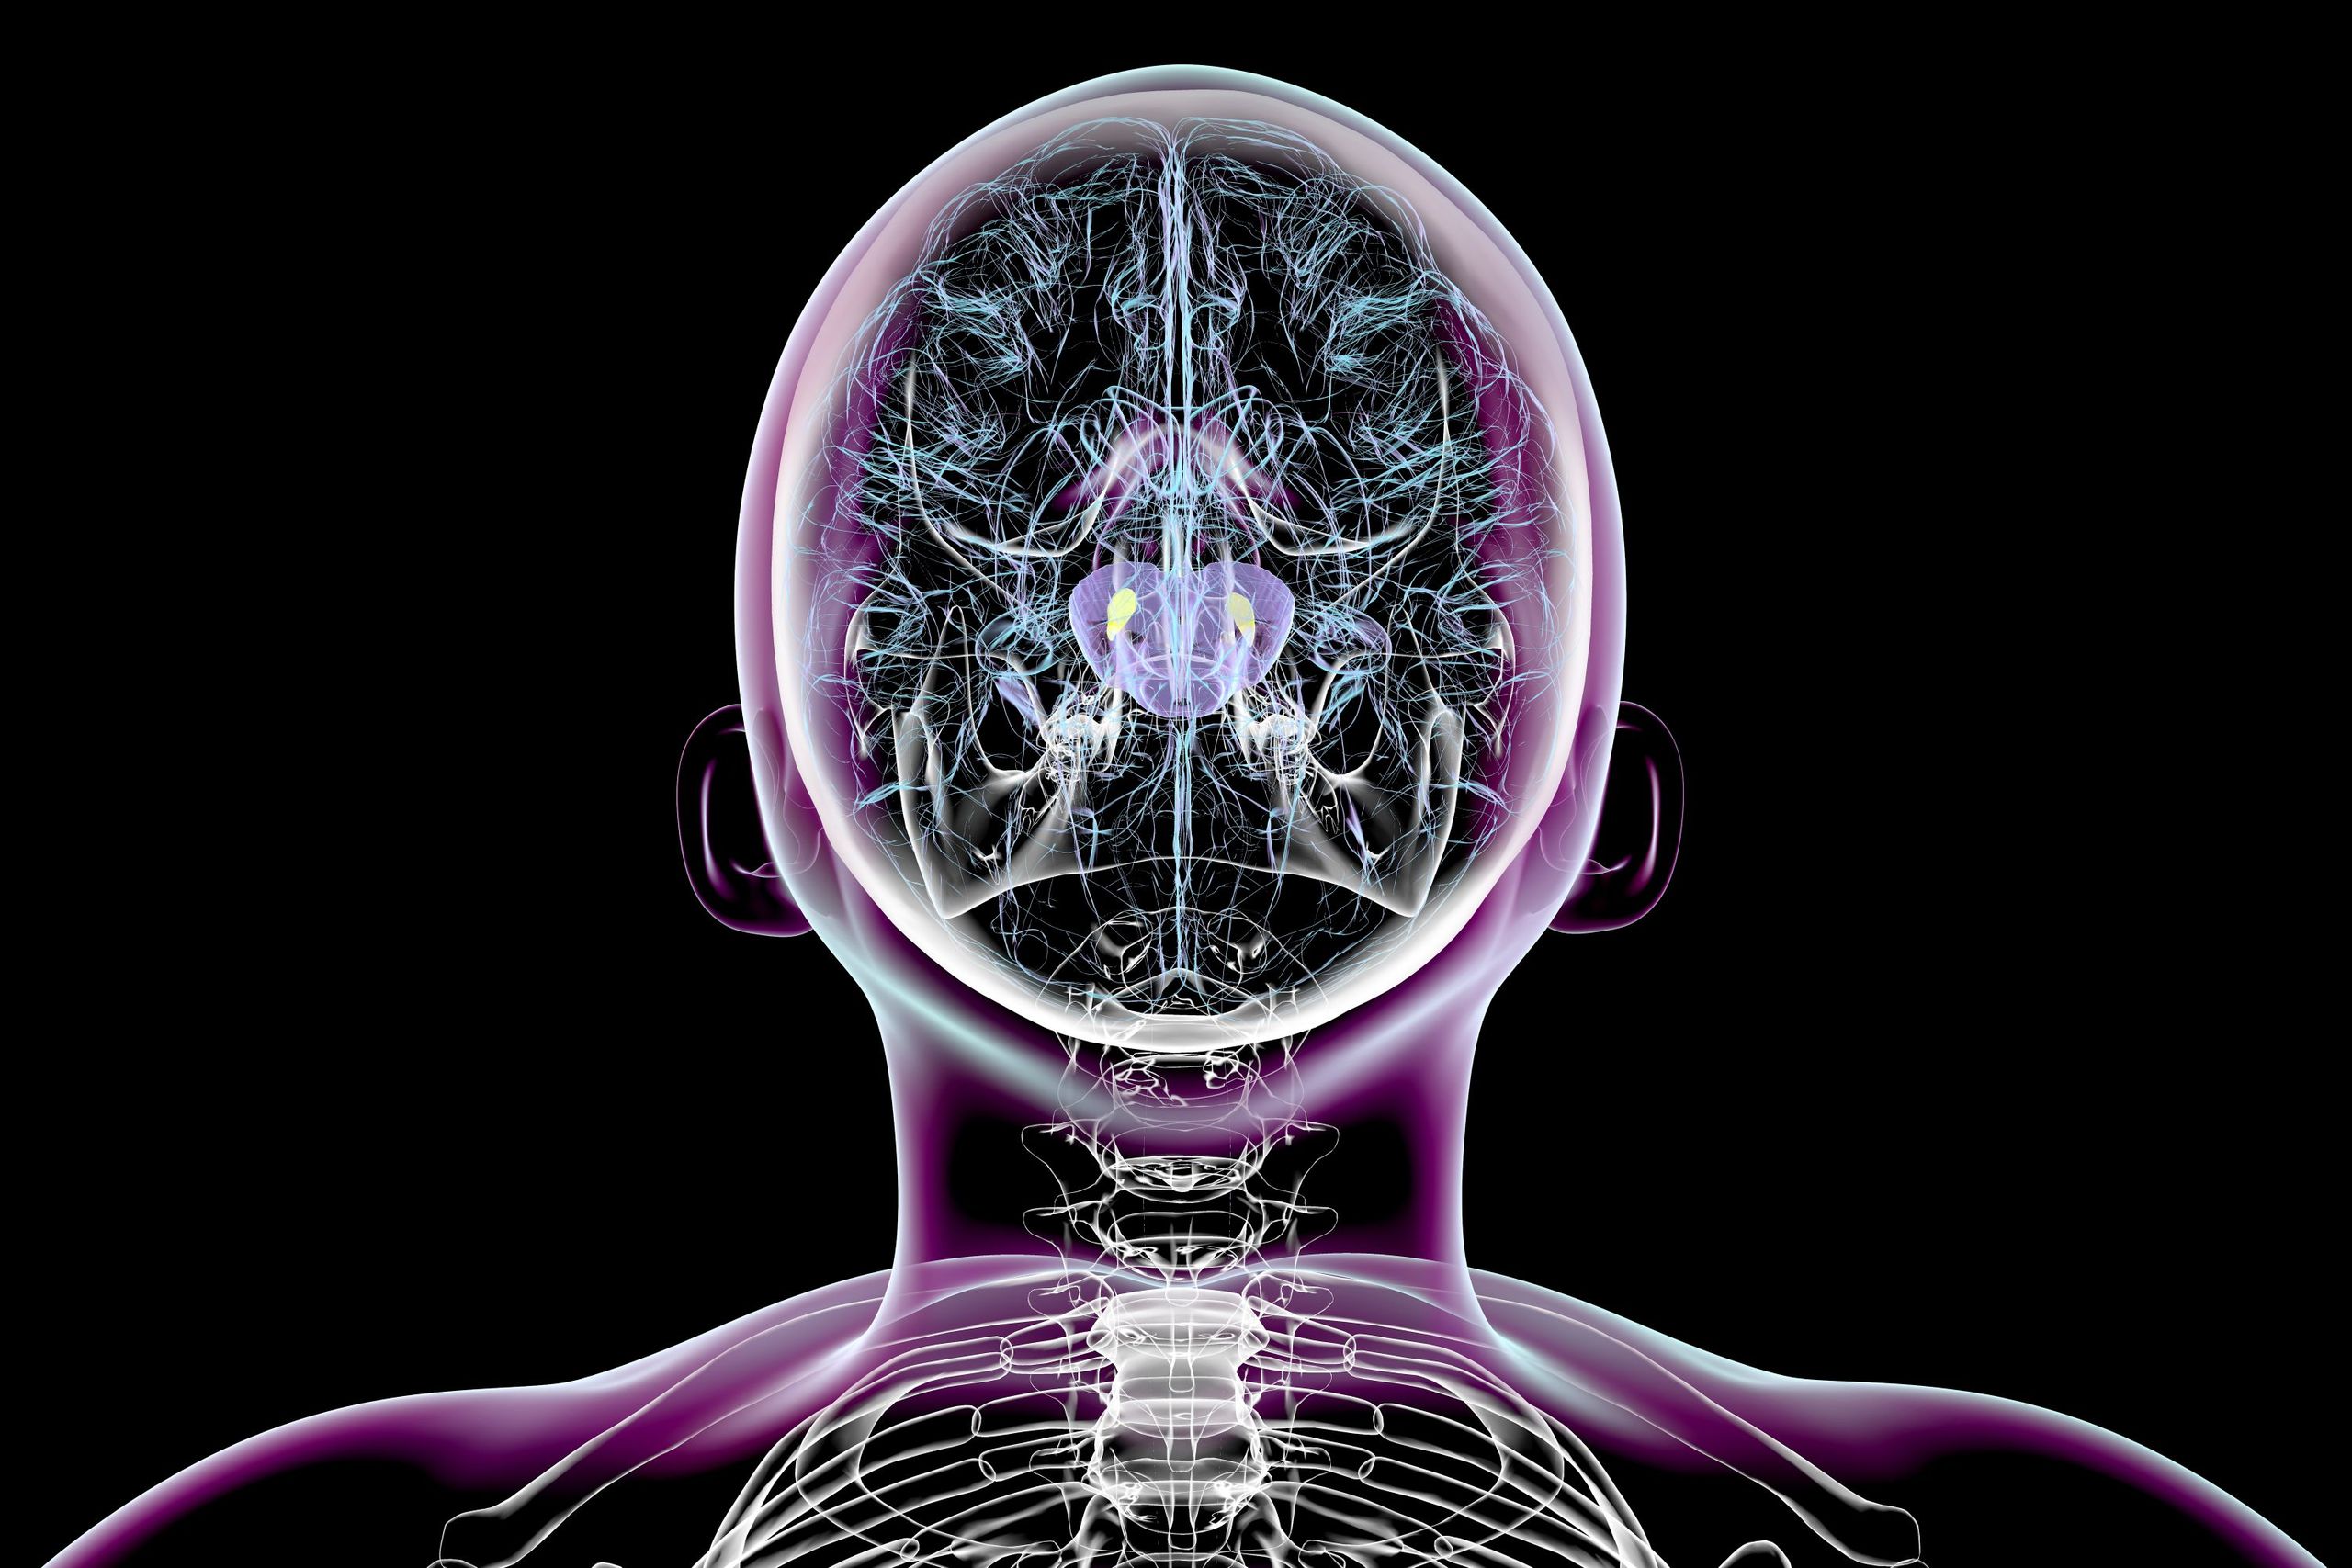

Sydney, Australia - Penyakit Parkinson adalah gangguan neurologis yang membuat sel otak penghasil dopamin mati, menyebabkan tremor dan kelambatan gerak. Hingga kini, belum ada obat yang bisa menyembuhkannya, sehingga para ilmuwan mencoba berbagai pendekatan untuk memperlambat penyakit ini.